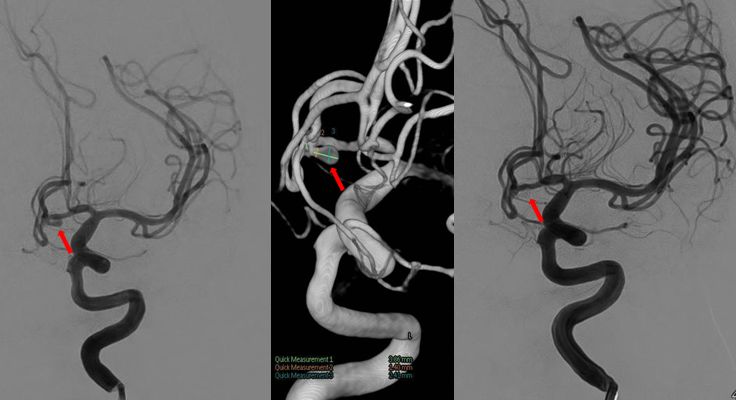

2018年5月4日,第二次支架辅助下栓塞

历经2次造影、2次开颅、2次栓塞

三个月后复查,未见复发,患者恢复良好

疑惑:第一次栓塞后,再次复查弹簧圈散开,原因?假性动脉瘤?

最终结果:复查造影动脉瘤未见复发,弹簧圈又回缩成一团。患者恢复良好。